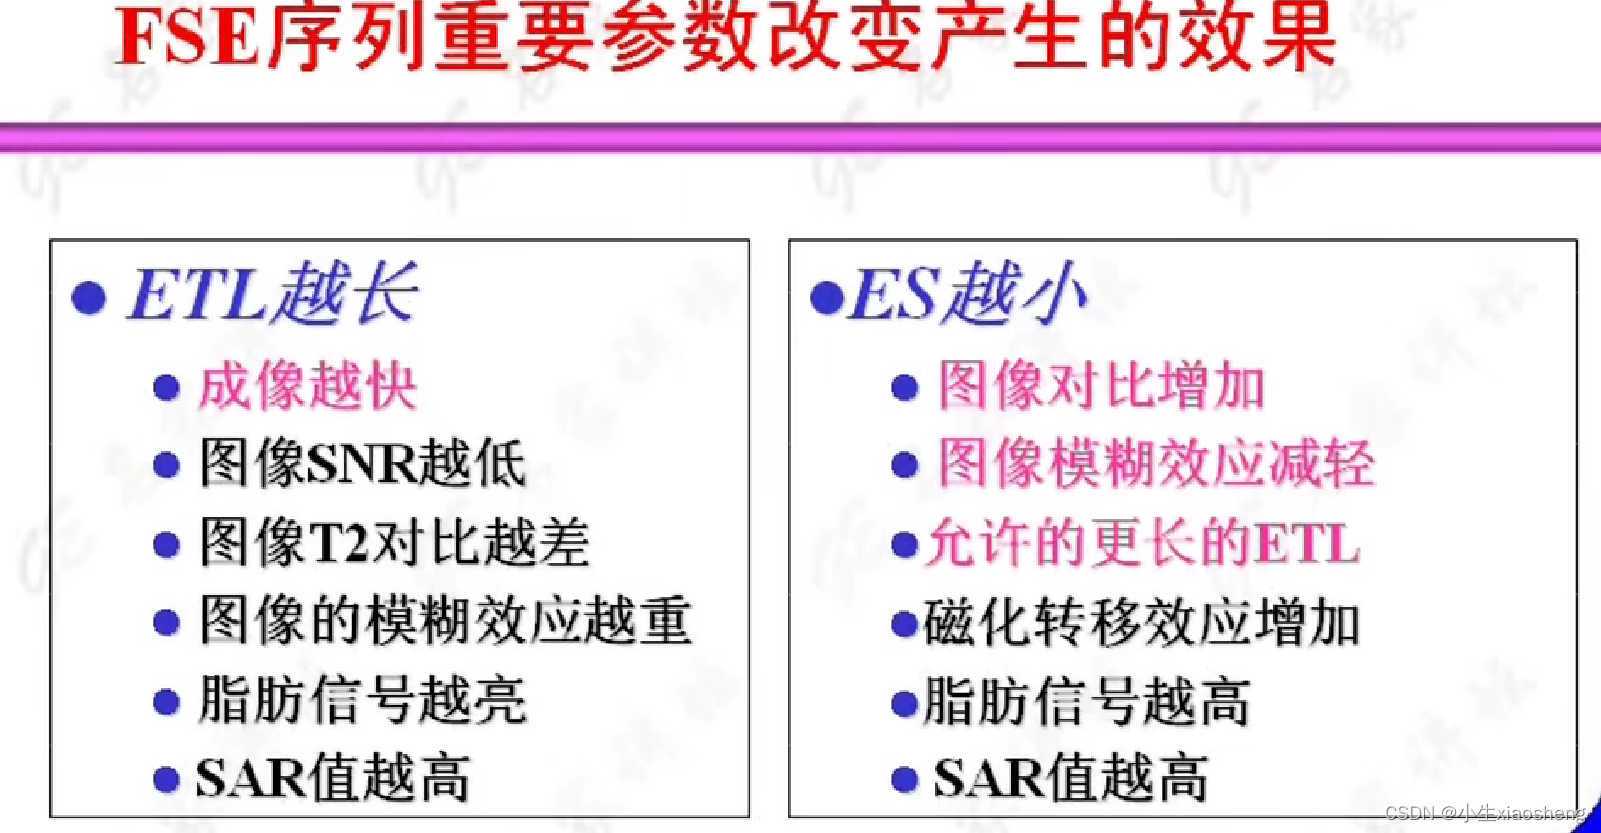

因为这里有很多的180度,所以一次能填充很多K空间线。两个90度之间的时间还是叫做TR,180度的个数叫做ETL,90度到中间个数的180度叫做有效TE,两个180度之间的叫做ES。

根据ETL的长度对FSE进行分类,不想了解这个分类所做的具体事情了😵